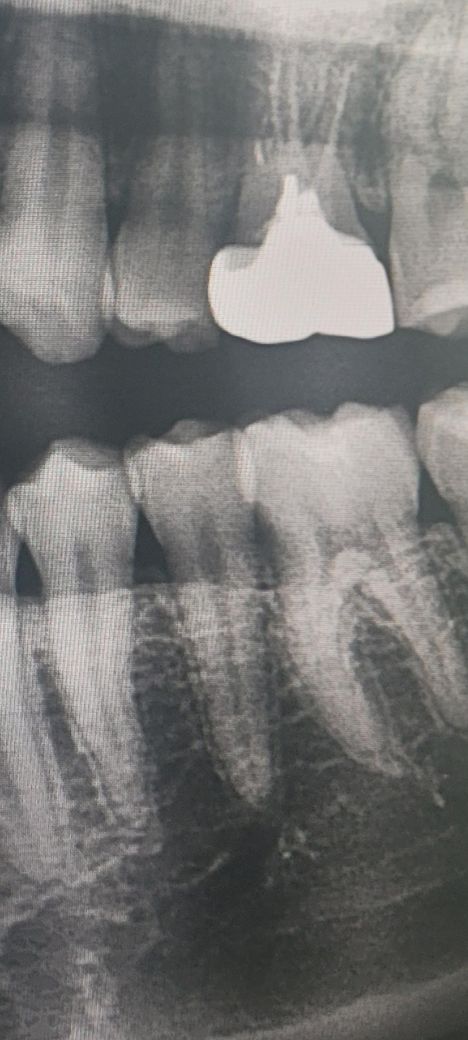

하악 소구치에 잇몸 염증이 생긴 걸까요?

씹을 때 아프지는 않고 그냥 있으면 살짝 아프고

괜찮다가 또 살짝 아픕니다.

8월에 치과갔을 때 별다른 이야기를 못들었는데

혹시 이상이 있는지 봐 주실 수 있으실까요?

또 2-3개월만에 뿌리염증이 생긴다거나 할 수도 있나요?

현재 사진상에서 특별히 문제는 모르겠습니다. 통증이 지속되면 치과 다시 가보시는 게 좋겟습니다.

사진으로 봤을 때는 뿔이 염증이 있는 것으로 보이진 않습니다. 잇몸부의 상태도 또한 크게 문제가 되는 것으로 보이진 않습니다. 해당 부위에 불편감이 있거나 출혈이 된다면 양치질을 할 때 양치를 꼼꼼하게 하시고 치실 사용해보세요.

골밀도가 낮아서 저렇게 보이는거 같습니다. 큰 문제가 잇어 보이는건 아닌거 같으니 너무걱정하지마세요.

현재 엑스레이 사진상으로는 특별히 뿌리 끝에 염증이 있다던지 병적인 소견은 없습니다. 정확한 건 치과가서 체크해보시기 바랍니다.

치아가 아니고 잇몸문제일 가능성도 있어보입니다.